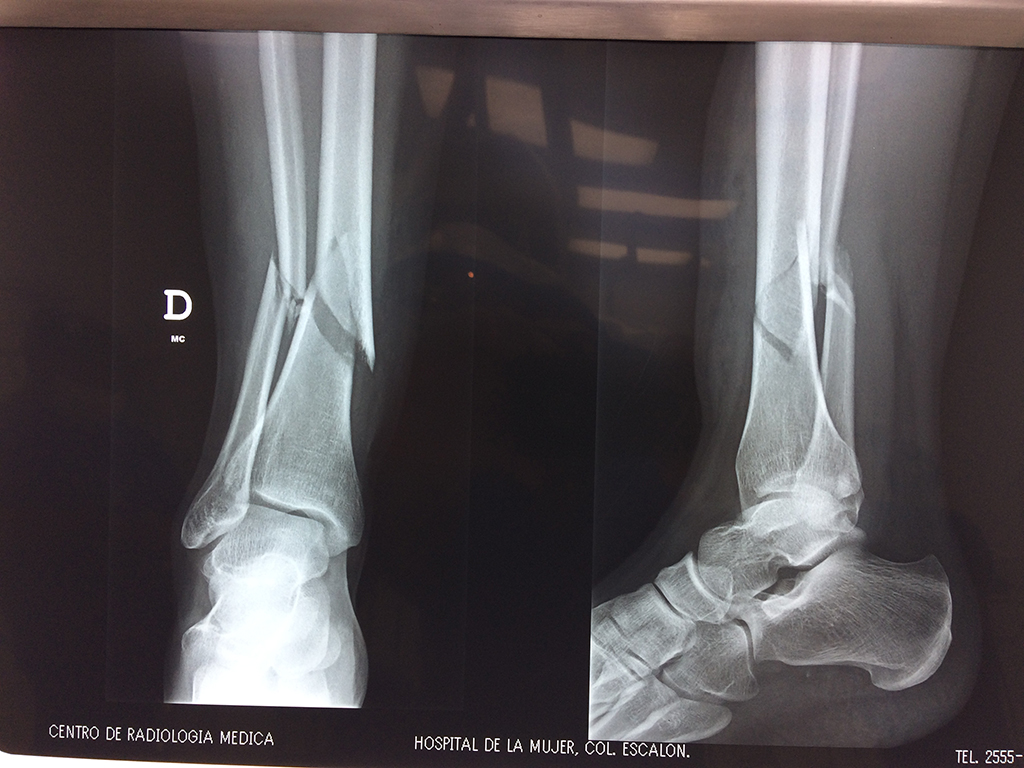

Cirugías de Codos - Perone y Tibia

Aunque cada uno de estos huesos puede fracturarse por separado, normalmente la rotura es una lesión que se produce de forma conjunta

La mayor parte de las roturas implican a la parte proximal del hueso (parte del hueso próximo a la rodilla) o a la parte distal (parte del hueso cerca del tobillo).

Debido a la fina cobertura de piel que recubre la tibia y el peroné, las fracturas generalmente son abiertas, es decir, el hueso roto rasga la piel, atravesándola. Las fracturas de tibia y peroné generalmente se producen por un fuerte impacto o torsión.